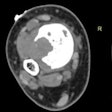

CT-guided biopsy aces bony lesion diagnosis